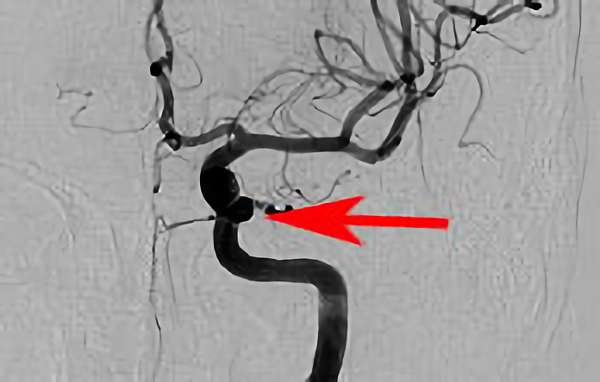

No.1631 手術前

No.1631 手術中

No.1631 手術後